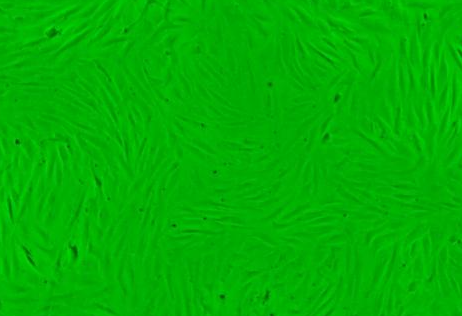

细胞名称:ChaGo-K-1 人肺支气管癌

培养条件:1640 +10% FBS

形 态:贴壁;上皮细胞样

ChaGo-K-1细胞提供原代/传代细胞,质量保证,生长状态良好,没有细菌 真菌 支原体等微生物污染。细胞一般以T25培养瓶包装,容积75ml细胞数量可达10的6次方左右。购买方收到细胞应当马上检查,如发现细胞状态不佳或者大部分死亡情况下,须当天联系我司。得到我技术确认后免费补发一株。一周内发现细胞有污染情况,请拍照记录并与销售部联系。